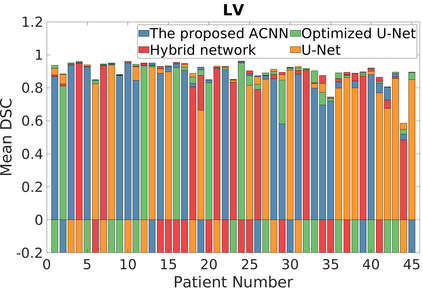

Deep Convolutional Neural Networks (DCNNs) are used extensively in biomedical image segmentation. However, current DCNNs usually use down sampling layers for increasing the receptive field and gaining abstract semantic information. These down sampling layers decrease the spatial dimension of feature maps, which can be detrimental to semantic image segmentation. Atrous convolution is an alternative for the down sampling layer. It increases the receptive field whilst maintains the spatial dimension of feature maps. In this paper, a method for effective atrous rate setting is proposed to achieve the largest and fully-covered receptive field with a minimum number of atrous convolutional layers. Furthermore, different atrous blocks, shortcut connections and normalization methods are explored to select the optimal network structure setting. These lead to a new and full-scale DCNN - Atrous Convolutional Neural Network (ACNN), which incorporates cascaded atrous II-blocks, residual learning and Fine Group Normalization (FGN). Application results of the proposed ACNN to Magnetic Resonance Imaging (MRI) and Computed Tomography (CT) image segmentation demonstrate that the proposed ACNN can achieve comparable segmentation Dice Similarity Coefficients (DSCs) to U-Net, optimized U-Net and hybrid network, but with significantly reduced trainable parameters due to the use of full-scale feature maps and therefore computationally is much more efficient for both the training and inference.